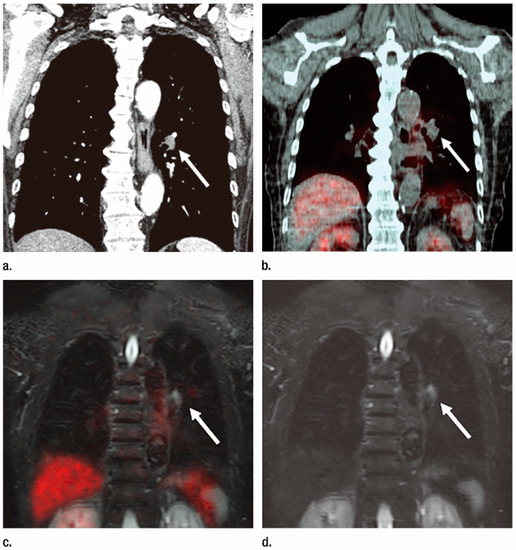

3.3. M-Factor Assessment